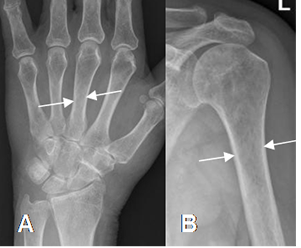

Fig 39. Densidad ósea normal.

A y B: Rx AP. Huesos normales, cuyo espesor cortical alcanza el 50% del diámetro de la diáfisis.